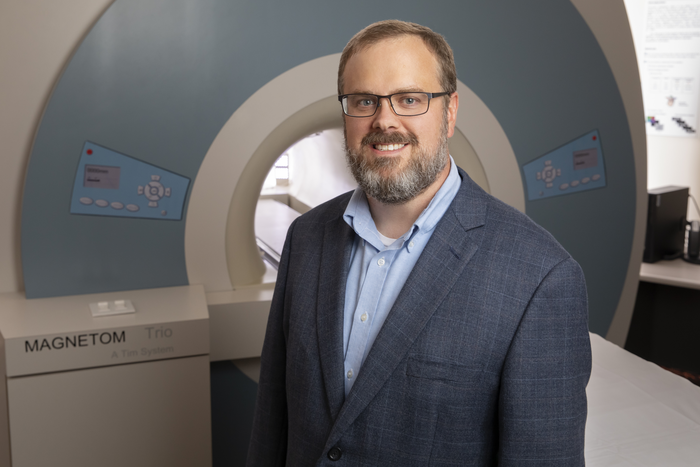

March 16, 2023, marks 50 years since Paul Lauterbur published his seminal Nature paper establishing zeugmatography — now ...